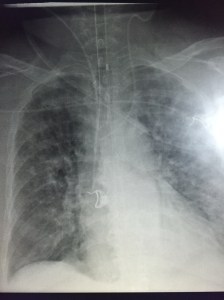

So a couple weeks ago I saw a patient in the ED who’d recently broken an ankle, had her foot put in a boot and managed conservatively and came back dyspneic and tachycardic. Here are a couple of clips:

She wasn’t very echogenic so I don’t have great clips of the heart but she had a dilated and hypocontractile RV with a McConnell’s sign (preserved apical contraction), small and hyper dynamic LV with septal flattening.

Based on hemodynamics, tachypnea and, to some degree, venous congestion, I decided to thrombolyse her using 1/2 dose lytics. Within a couple of hours her HR decreased to the 90’s and BP rose to 110 systolic. Echographically, however, the IVC/RV findings remained similar, but the HPVG decreased. By the next day, HPVG was altogether gone, lactate had resolved and dyspnea was significantly better.